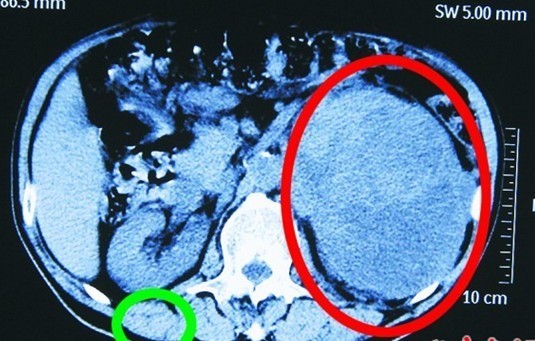

患者王先生的腎臟(圖中綠圈處)和巨大腎腫瘤(圖中紅圈處)。